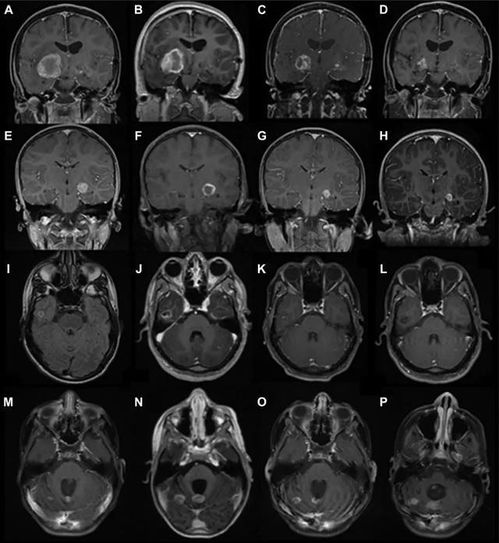

肿瘤生长速度可通过影像学(如CT、MRI)定期测量,或使用RECIST标准评估体积变化。内镜超声能精准测量肿瘤浸润,而CHOI标准结合密度变化可判断治疗效果及耐药性。